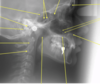

Mandibular Canal

Contains the inferior alveolar nerve and blood vessels that extend from the mandibular foramen ro the mental foramen

Mandibular Canal

Contains the inferior alveolar nerve and blood vessels that extend from the mandibular foramen ro the mental foramen

Can run close to third molar roots, causing problems upon extraction